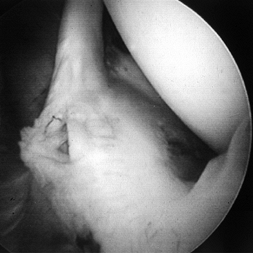

superior labral tears from anterior to posterior (SLAP lesions) (6) (Fig. 77.2; see also COLOR FIG. 77.2).

Figure 77.2. (See COLOR FIG. 77.2.) Superior labral tear from anterior to posterior (SLAP lesion). -